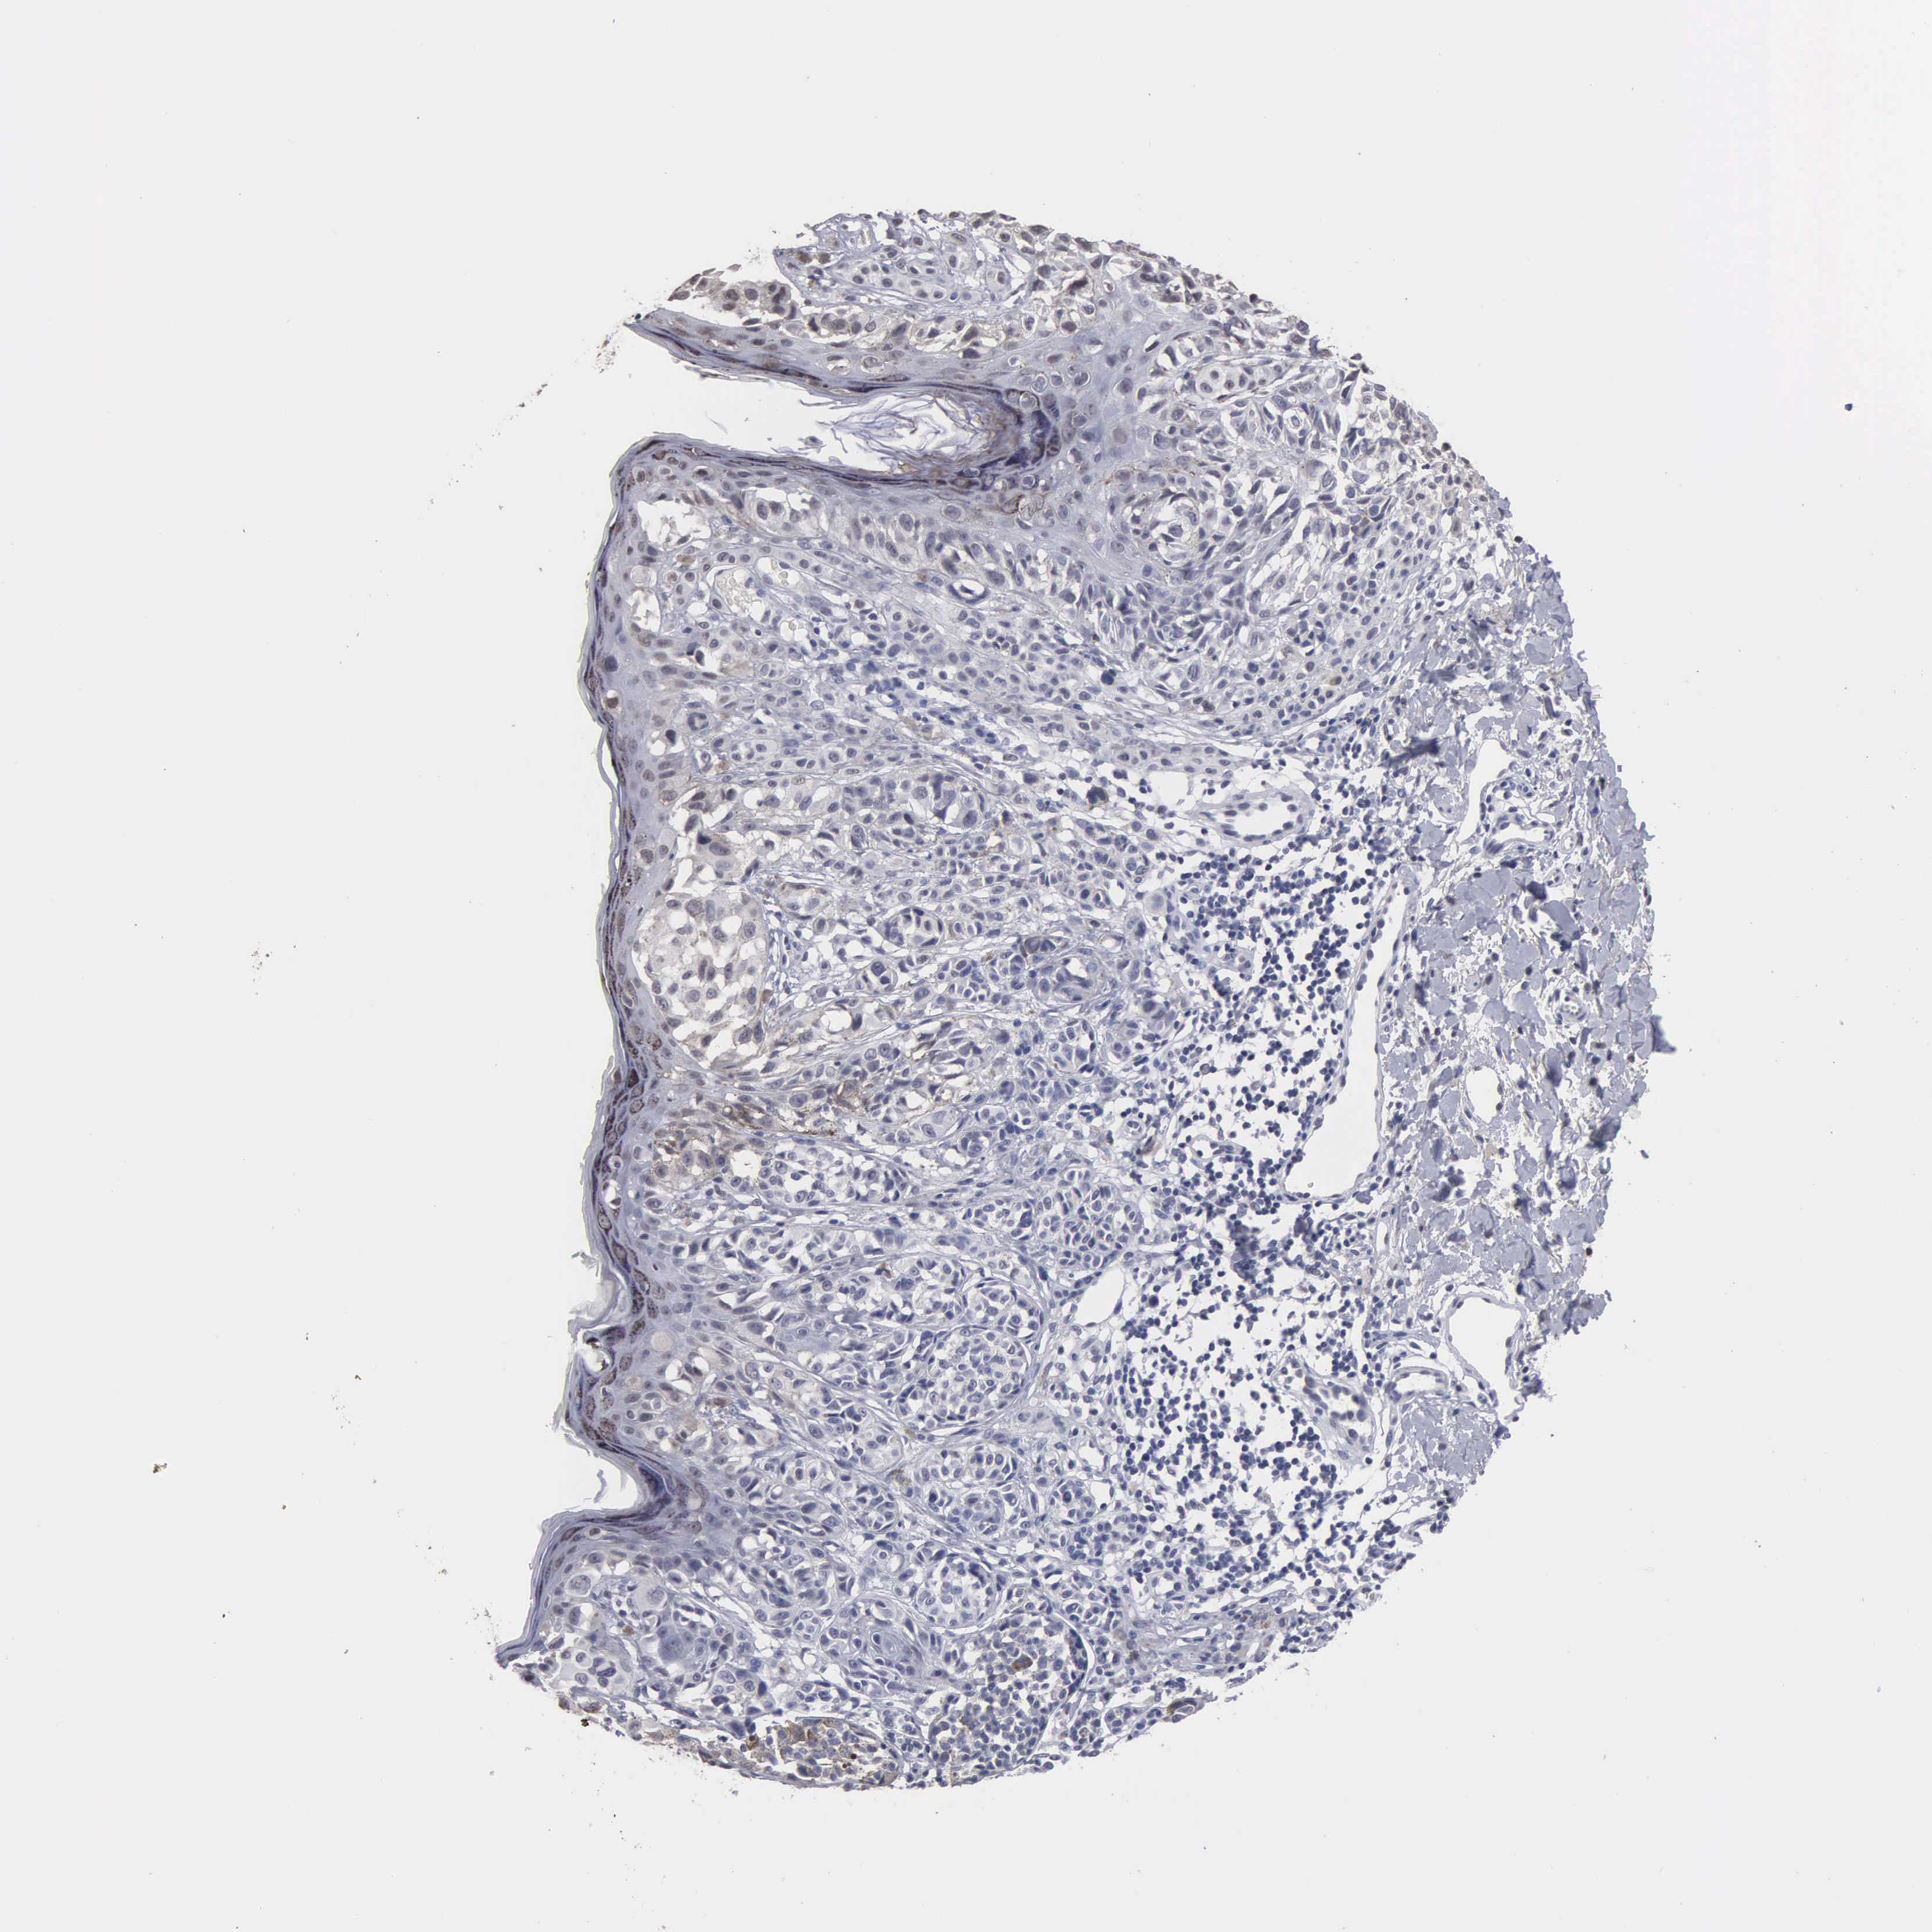

MELANOMA - Protein expressioni

A mouse-over function shows sample information and annotation data. Click on an image to view it in a full screen mode. Samples can be filtered based on level of antibody staining by selecting one or several of the following categories: high, medium, low and not detected. The assay and annotation is described here.

Antibody stainingi

Antibody staining in the annotated cell types in the current human tissue is reported as not detected, low, medium, or high, based on conventional immunohistochemistry profiling in selected tissues. This score is based on the combination of the staining intensity and fraction of stained cells.

Each image is clickable and will lead to virtual microscopy that enables deeper exploration of all samples and also displays staining intensity scores, fraction scores and subcellular localization as well as patient and tissue information for each sample.

Antibody HPA000728

Antibody HPA076321

Staining

High

Medium

Low

Not detected

Intensity

Strong

Moderate

Weak

Negative

Quantity

>75%

75%-25%

<25%

None

Location

Nuclear

Cytoplasmic/membranous

Cytoplasmic/membranous,nuclear

Malignant melanoma, NOS

Malignant melanoma, Metastatic site